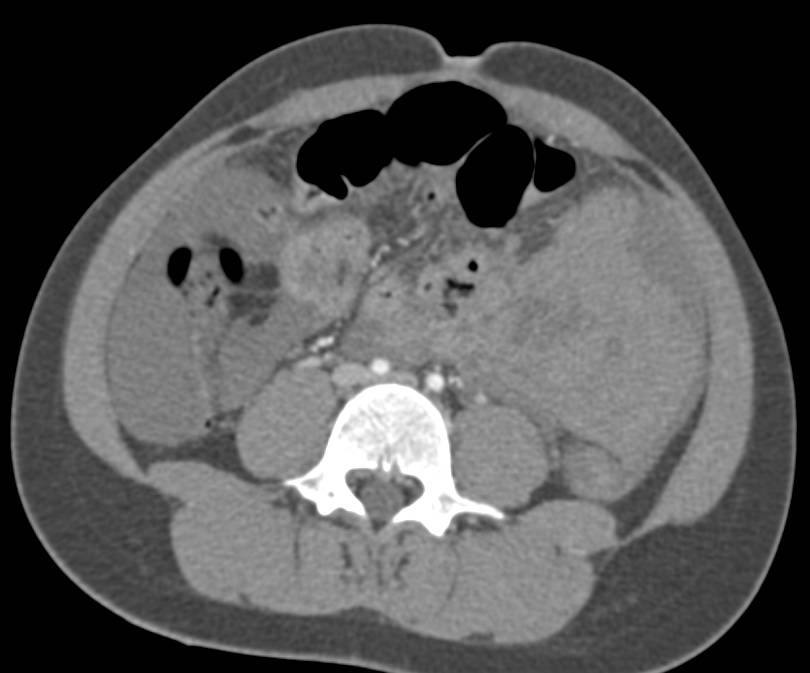

Abdominal Liposarcoma